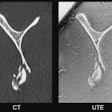

Montin and colleagues used data from the Human Connectome Project-Aging in a study that included T1- and T2-weighted brain images from 716 healthy adults; this data was used to gather 18,324 radiomics features from areas of the brain understood to be highly affected in the course of normal aging: the bilateral hippocampus, the putamen, and the caudate and to train a stacking regressor machine-learning model (a machine-learning technique that combines predictions of multiple estimators, Montin said). The model included eight regressors: Lasso, random forest, k-nearest neighbors, gradient boosting, AdaBoost, HistGradientBoostingRegressor, and MLPRegressor.

The predictive model using the stacking regressor was trained on only 20 radiomic features --which "supports our hypothesis that these three main brain subcortical areas are enough to provide key information for machine learning-based aging prediction," Montin's team noted -- and estimated brain age with a mean absolute error value of 4.7 years.